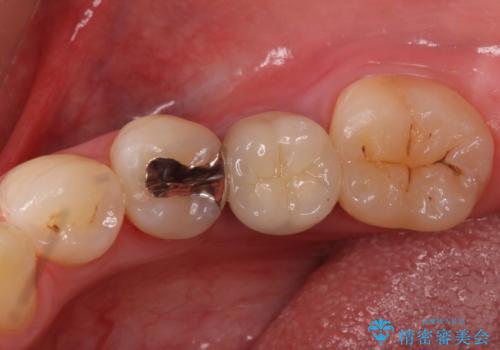

銀の詰め物 セラミックへのやり替え

- 下の奥の銀歯を白くしたいとのことで来院されました。

セラミックインレーでの治療を行いました。

- 左下5 セラミックインレー 77,000円費用は治療当時の料金となります